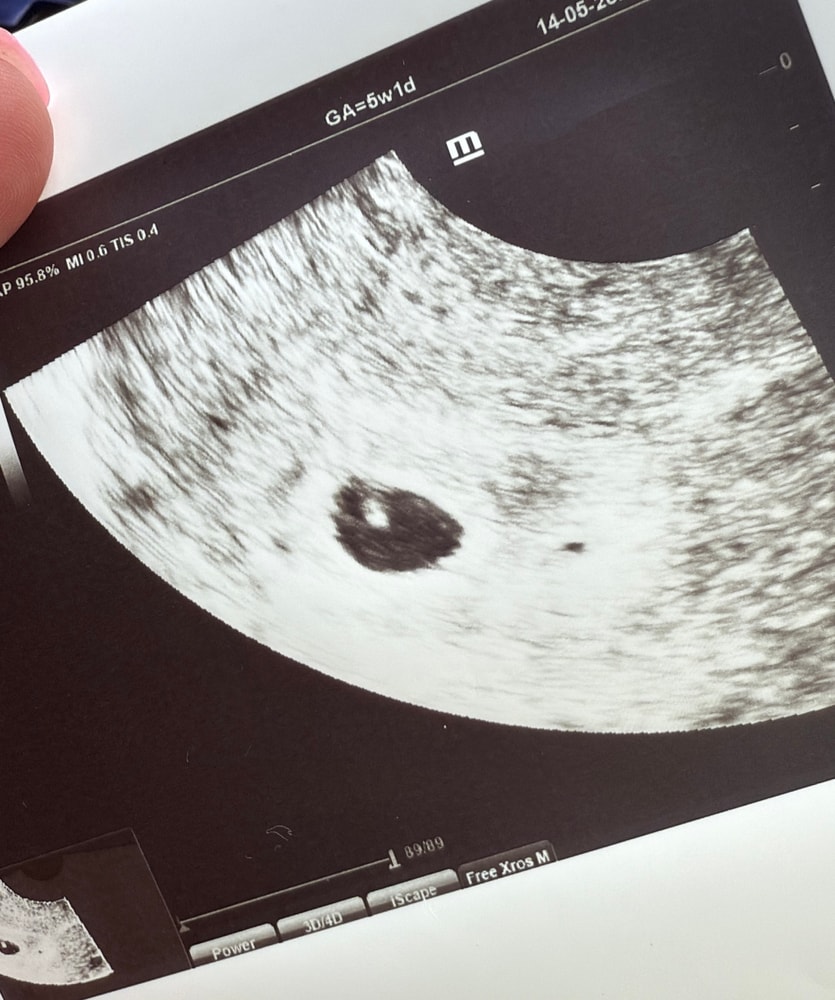

Итак, сегодня ходила на первое свидание с малышариком. По узи подтвердили маточную беременность сроком 5 недель. ПЯ - 11 мм (4 Нед 6 дн), КТР - 2,9 мм (5 Нед 2 дн), желточный мешок - 2 мм, хорион кольцевидный. Нашли отслойку, написано: «по передней стенке участок отслойки 3,1*2,1 мм». Кто в курсе, насколько это опасно и что с этим делать? Мазало коричневым 9 и 11 мая, после этого ничего не беспокоило.

Сказали, что сердцебиение вроде визуализируется, но очень рано еще. Записали на 22.05 на повторное узи. Господи, пусть все будет хорошо 🙏🙏🙏